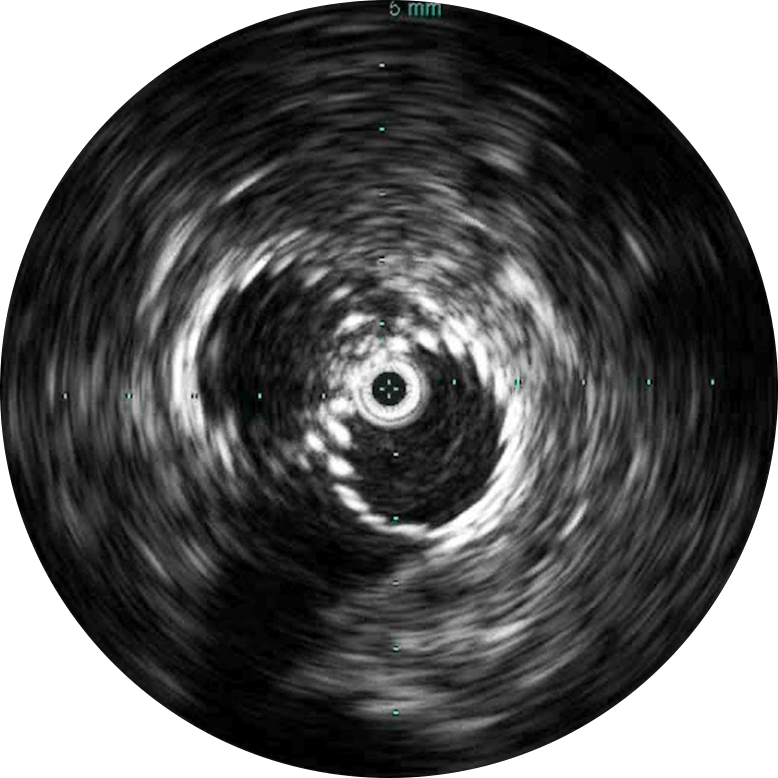

Визуализация на 360 ̊ способствует лучшему пониманию заболевания и придаточных структур, к которым также относятся уровень компрессии, остеофиты, тромбы и прочее.

Цифровой катетер для ВСУЗИ Visions PV (0,035 дюйма) дополняет стандартные инструменты проведения ангиографических процедур, обеспечивая оценку морфологии кровеносных сосудов и их визуализацию в поперечном сечении. Благодаря рабочей длине, равной 90 см, и максимальному диаметру визуализации, равному 60 мм, для инвазивных процедур с использованием проводника диаметром 0,035 дюйма, устройство облегчает диагностику заболеваний вен и периферических артерий и помогает врачам выбрать правильный подход к лечению с учетом индивидуальных потребностей пациента.